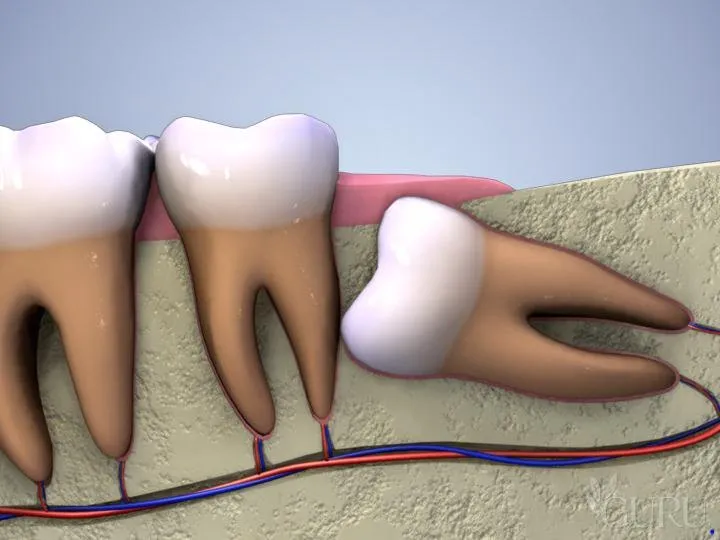

Răng số 8 mọc lệch là một trong những vấn đề nha khoa phổ biến, gây ra nhiều khó chịu và ảnh hưởng nghiêm trọng đến sức

Răng số 8 có nên nhổ không là thắc mắc phổ biến của nhiều người khi gặp phải các vấn đề liên quan đến răng khôn. Răng